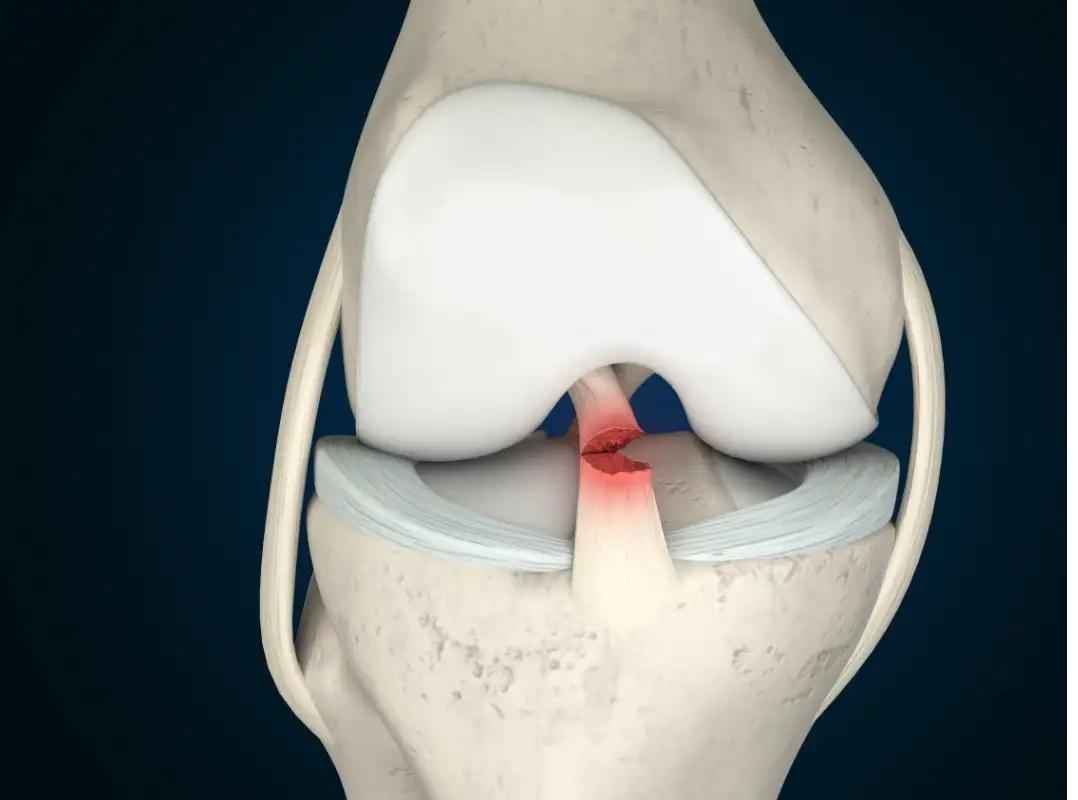

每位運動員成功背後,均曾受傷患困擾,並成功克服,重返賽場。以江旻憓為例,她的左腳及右腳便曾出現十字韌帶斷裂,需施行手術。

甚麼是十字韌帶斷裂?它分為兩類:第一類是非接觸性,第二類是接觸性。江旻憓第一次十字韌帶斷裂時,是沒有出現任何撞擊或失足絆倒,她只是在訓練期間,輕輕跳起著地,便出現斷裂。江旻憓第二次十字韌帶斷裂,則是跌倒受傷。

在足球界或籃球圈,球員跌倒時,均會產生3種力量,分別是:

- 內彎;

- 內旋;

- 內彎內旋相結合。

倘若上述3種力量同時出現,便可導致十字韌帶斷裂。

前十字韌帶康復需多少時間?一般需要6至9個月時間。即使是使用一些方法加快「復合」,亦需時3至6個月。所以,若然大家細心留意江旻憓從受傷到重返賽場時間,便發現她的康復時間,較一般人為快。